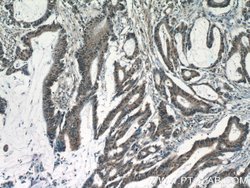

| Applications | Immunohistochemistry (Paraffin), Western Blot |

This KIAA0087 antibody gives a 40 kDa band in Western Blot.

KIAA0087 (KIAA0087 LncRNA) is an RNA Gene, and is affiliated with the non-coding RNA class. Diseases associated with KIAA0087 include Endometrial Cancer and Pancreatic Cancer.Specifications